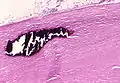

Due to the asbestos fibers' natural resistance to digestion, some macrophages are killed and others release inflammatory chemical signals, attracting further lung macrophages and fibrolastic cells that synthesize fibrous scar tissue, which eventually becomes diffuse and can progress in heavily exposed individuals. This tissue can be seen microscopically soon after exposure in animal models. Some asbestos fibers become layered by an iron-containing proteinaceous material (ferruginous body) in cases of heavy exposure where about 10% of the fibers become coated. Most inhaled asbestos fibers remain uncoated. About 20% of the inhaled fibers are transported by cytoskeletal components of the alveolar epithelium to the interstitial compartment of the lung where they interact with macrophages and mesenchymal cells. The cytokines, transforming growth factor beta and tumor necrosis factor alpha, appear to play major roles in the development of scarring inasmuch as the process can be blocked in animal models by preventing the expression of the growth factors.[20][21] The result is fibrosis in the interstitial space, thus asbestosis.

The arrow points to an uncoated segment of asbestos fiber in this ferruginous body.